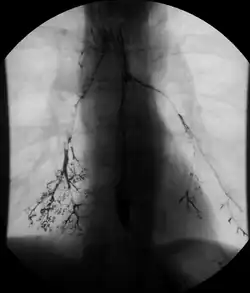

In addition to fasting for 8 hours prior to examination, a laxative may also be necessary for bowel preparation and cleansing.[12] The main aim of this study is to distend the proximal bowel through infusion of large amount of barium suspension. Otherwise, the distension of distal small bowel is generally similar with small bowel follow-through. Therefore, there is a need to pass a tube through the nose into the jejunum (nasojejunal tube) to administer large amount of contrast. This can be unpleasant to the subject, requires more staff, longer procedural time, and higher radiation dose when compared to small bowel follow-through. The indications for enteroclysis are generally similar to small bowel follow-through. Barium suspensions such as diluted E-Z Paque 70% and Baritop 100% can be used. After that, 600 ml of 0.5% methylcellulose is administered after 500 ml of 70% barium suspension is given. Bilbao-Dotter tube and Silk tube can be used to administer barium suspension. The subject should be fasted overnight, any antispasmodic drugs should be stopped one day before the examination, and Tetracaine lozenges can be used 30 minutes before the procedure to numb the throat for nasojejunal tube insertion.[13]

The filling of the small intestines can be viewed continuously using fluoroscopy, or viewed as standard radiographs taken at frequent intervals. The technique is a double-contrast procedure that allows detailed imaging of the entire small intestine. However, the procedure may take 6 hours or longer to complete and is quite uncomfortable to undergo.[23]